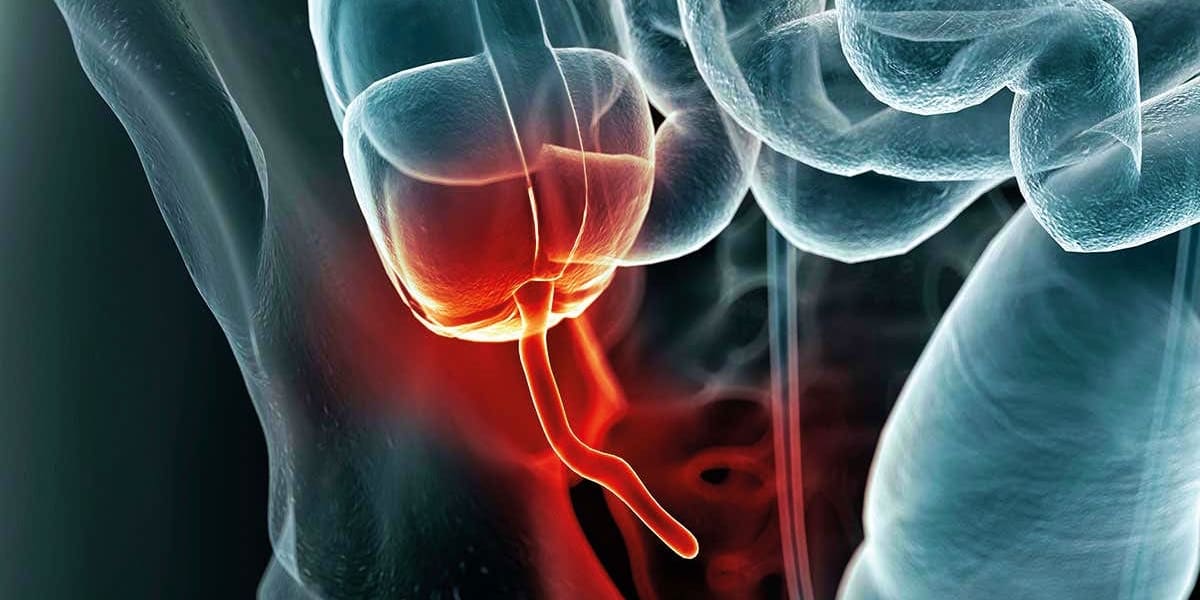

35. The Human Appendix

Isn’t it weird how humans have been around for thousands of years and still have an appendix? For the longest time, we assumed that it was some random human evolutionary issue. Most of the time, mammals are especially known for dropping anything that is actually a problem for our overall lifestyle. Why did this little weird thing remain inside of us the entire time?

Contrary to popular belief, the appendix does so much more than we first thought. The main role of it today is to store good bacteria, which is then accessed by the colon and intestines for better overall health in the gastrointestinal tract. It helped to maintain gut flora as a result of this and even helps the immune system too. Seriously, it’s highly underrated.